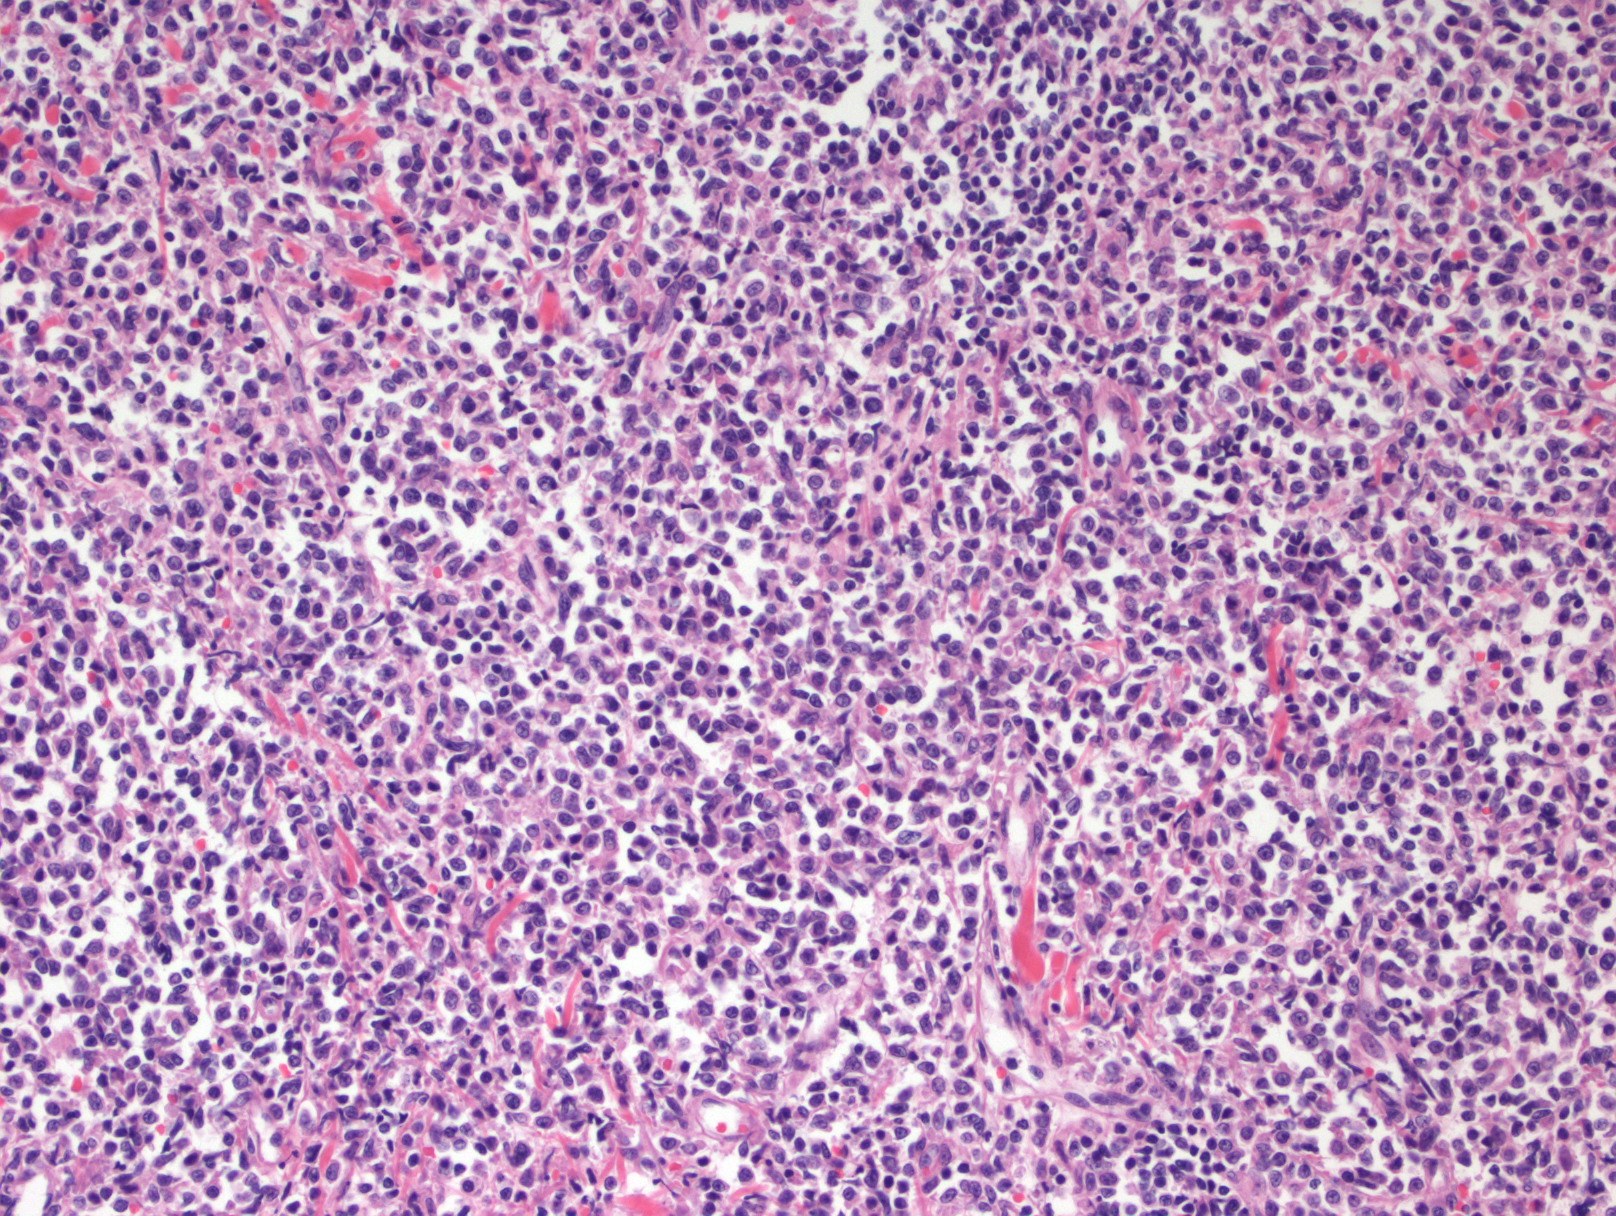

形态学:肿瘤细胞呈现弥漫生长,具母细胞特征(可类似淋巴母细胞或髓系母细胞):中等大小、形态单一、核轻度不规则、染色质细腻、一到多个核仁、胞质细少,无颗粒。在皮肤,通常浸润真皮,最终延及皮下,但不累及表皮;在骨髓,呈现稀少或成片间质浸润,涂片有时可见肿瘤细胞有膜下微小空泡及包膜伪足;在淋巴结,常侵犯髓区或滤泡间(白血病侵犯模式)。一般不出现凝固性坏死和血管中心性浸润。